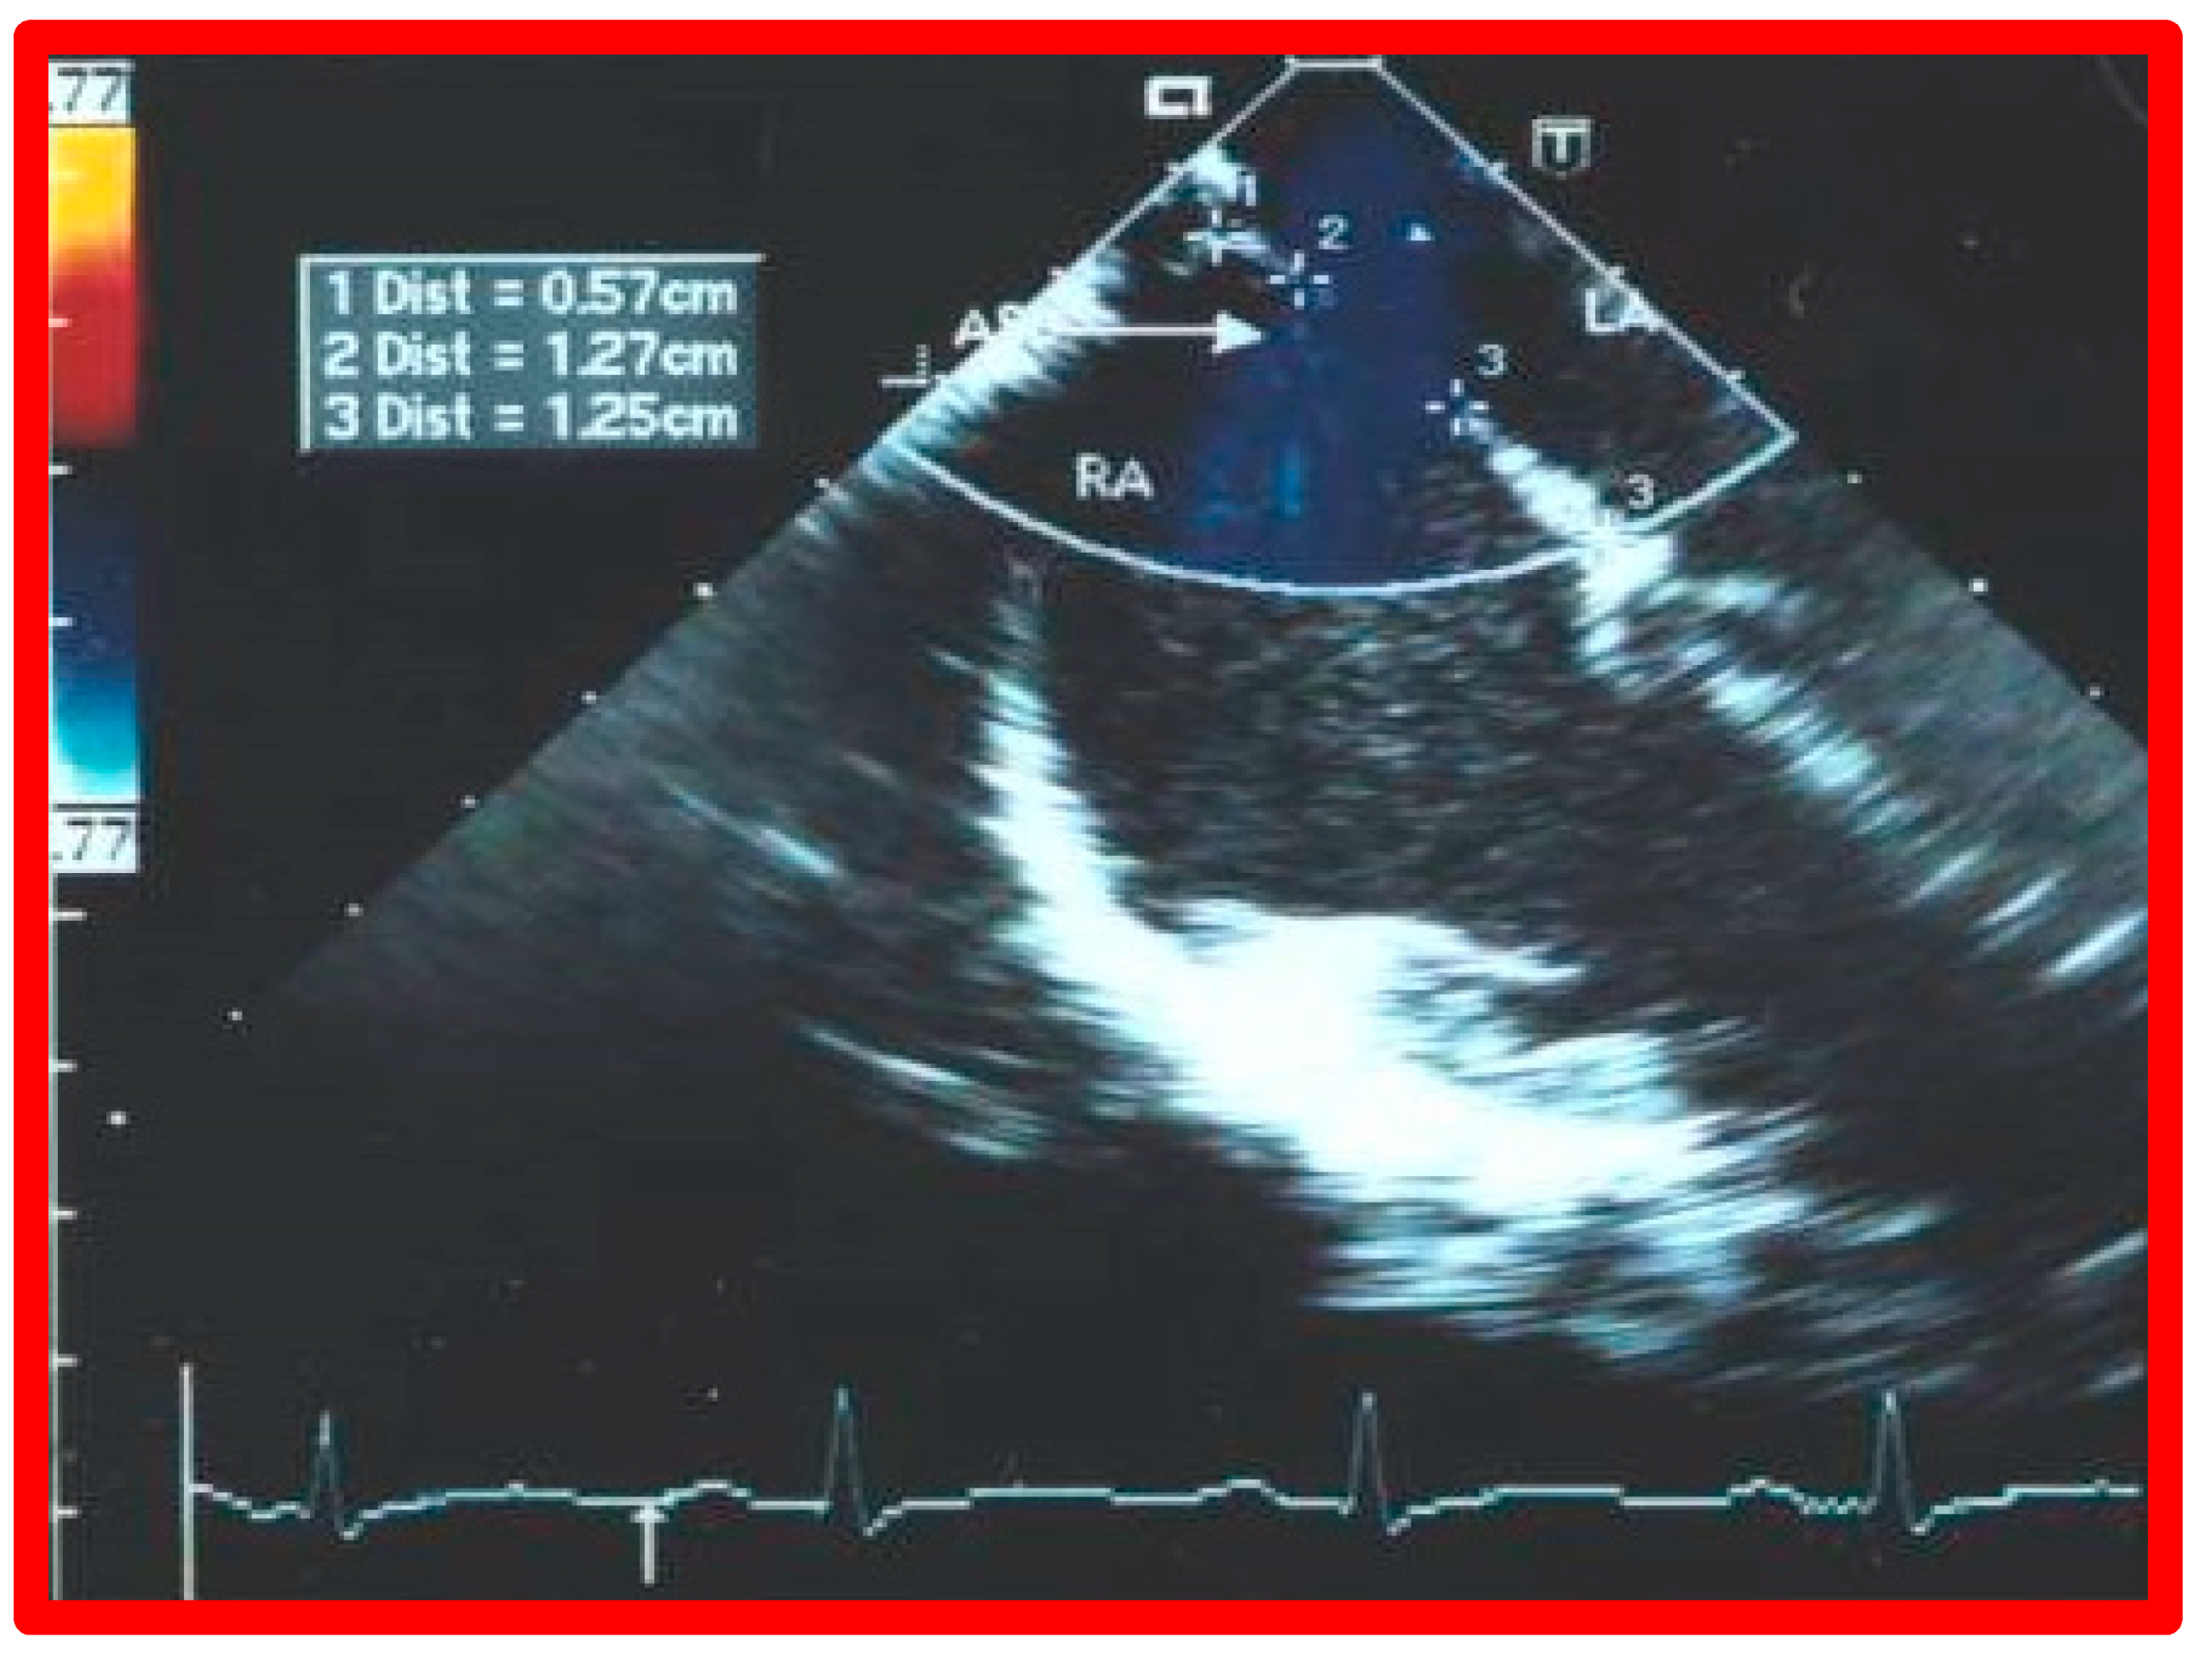

6. TEE and ICE

7. Balloon Sizing